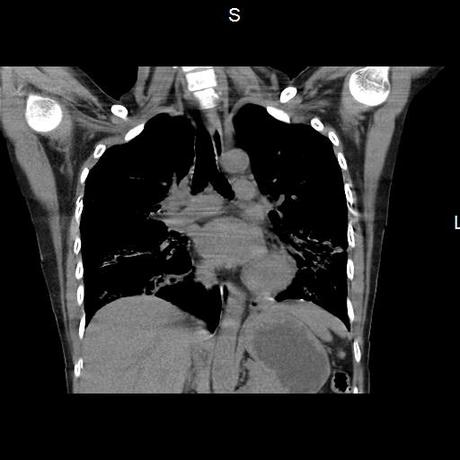

Se realiza volumen de tórax en fase simple, desde los opérculos torácicos hasta los hemidiafragmas, observándose:

El parénquima pulmonar con areas parcheadas difusas en vidrio despulido combinadas con otras areas hipodensas de baja atenuación debidas a atrapamiento aéreo y engrosamiento intersticial y zonas de fibrosis de predominio en lóbulos medios e inferiores de ambos pulmones.

- LOS HALLAZGOS PUEDEN ESTAR EN RELACIÓN A NEUMOPATIA INTERSTICIAL PROBABLE ETIOLOGIA HIPERSENSITIVA VS AUTOINMUNE/BACTERIANA/FUNGICA.